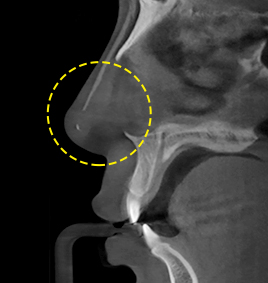

กรณีที่ 1เมื่อกอร์เทกซ์หนาจนกดทับผิว

ถอดกอร์เทกซ์ออกแล้วแทนที่ด้วยวัสดุที่ทำจากซิลิโคน ขึ้นอยู่กับสภาพผิวควบคู่ไปกับศัลยกรรมปลายจมูก